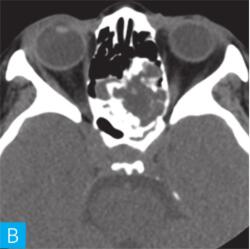

CT检查:检查设备为16层CT,病人采取仰卧位,扫描范围包括双侧鼻窦。扫描参数:层厚2.5mm,120kV,150mA,矩阵512×512。观察图像:软组织窗窗宽300HU,窗位60HU;骨窗窗宽2000HU,窗位400HU,见图1。

图1 鼻窦CT:A. CT横断面(骨窗);B. CT横断面(软组织窗);C. CT冠状面(骨窗);D. CT冠状面(软组织窗)

答案A 解析:结合CT横轴位及冠状位图像,该病变位于后组筛窦,不难判断。

答案D 解析:该病例病变周围骨质在原有后组筛窦结构基础上出现轻度的骨质膨胀性改变,周围骨质可见明显硬化,故D为最佳答案。

CT平扫示后组筛窦区见轻度膨胀性骨质破坏,内部密度混杂,可见斑片状、分隔状骨质密度影,部分呈磨玻璃改变,病变边缘清晰,可见薄层骨壳及硬化边。

发现病变较为容易,主要分析其病变的良恶性。本病例基本征象为病变区域呈轻度膨胀性骨质破坏,邻近骨质呈轻度压迫性骨质吸收,边缘可见硬化边,提示病变慢性进展过程,病变内部密度欠均匀,以软组织密度以及磨玻璃样高密度为主。

本病例CT上特点为轻度膨胀性压迫性骨质吸收,边缘骨质见硬化边,呈薄层骨壳表现,提示肿瘤良性可能;病变内部密度不均匀,可见骨性间隔及斑片状磨玻璃骨性密度影,提示病变可能为骨纤维源性肿瘤或肿瘤样病变。

除此之外,我们需注意病变内部变异出现了大片状磨玻璃样骨性高密度影;一般来说,骨内病变出现磨玻璃密度,极大可能提示病变可能为骨纤维源性肿瘤,其病理上多数是由于纤维化骨不完全所致。需要了解的是,发生于颌面骨的骨纤维源性良性肿瘤或肿瘤样病变较为常见的是骨化性纤维瘤和骨纤维异常增殖症,两者在病理水平较难鉴别,但在影像学表现上有各自的特点。骨化性纤维瘤主要发生于颌面骨,一般以单骨受累为主,因组织分化不同,内部成分多混杂,可出现软组织密度、囊性密度、磨玻璃密度以及骨性密度等;另外骨化性纤维瘤外周一般会有较为明显的骨壳包绕,也是诊断要点。而发生于颌面骨的骨纤维异常增殖症,一般呈多骨受累,同时骨质膨胀变形较骨化性纤维瘤更为明显。

与骨化性纤维瘤比较,骨纤维异常增殖症骨质密度相对均匀,主要以磨玻璃样密度为主,外周出现骨壳的概率也较小。结合本病例,病变主要以单骨受累为主,呈轻度膨胀改变,其内部密度不均伴有磨玻璃密度改变,边缘呈薄层骨壳样改变,应该考虑到骨化性纤维瘤的诊断。